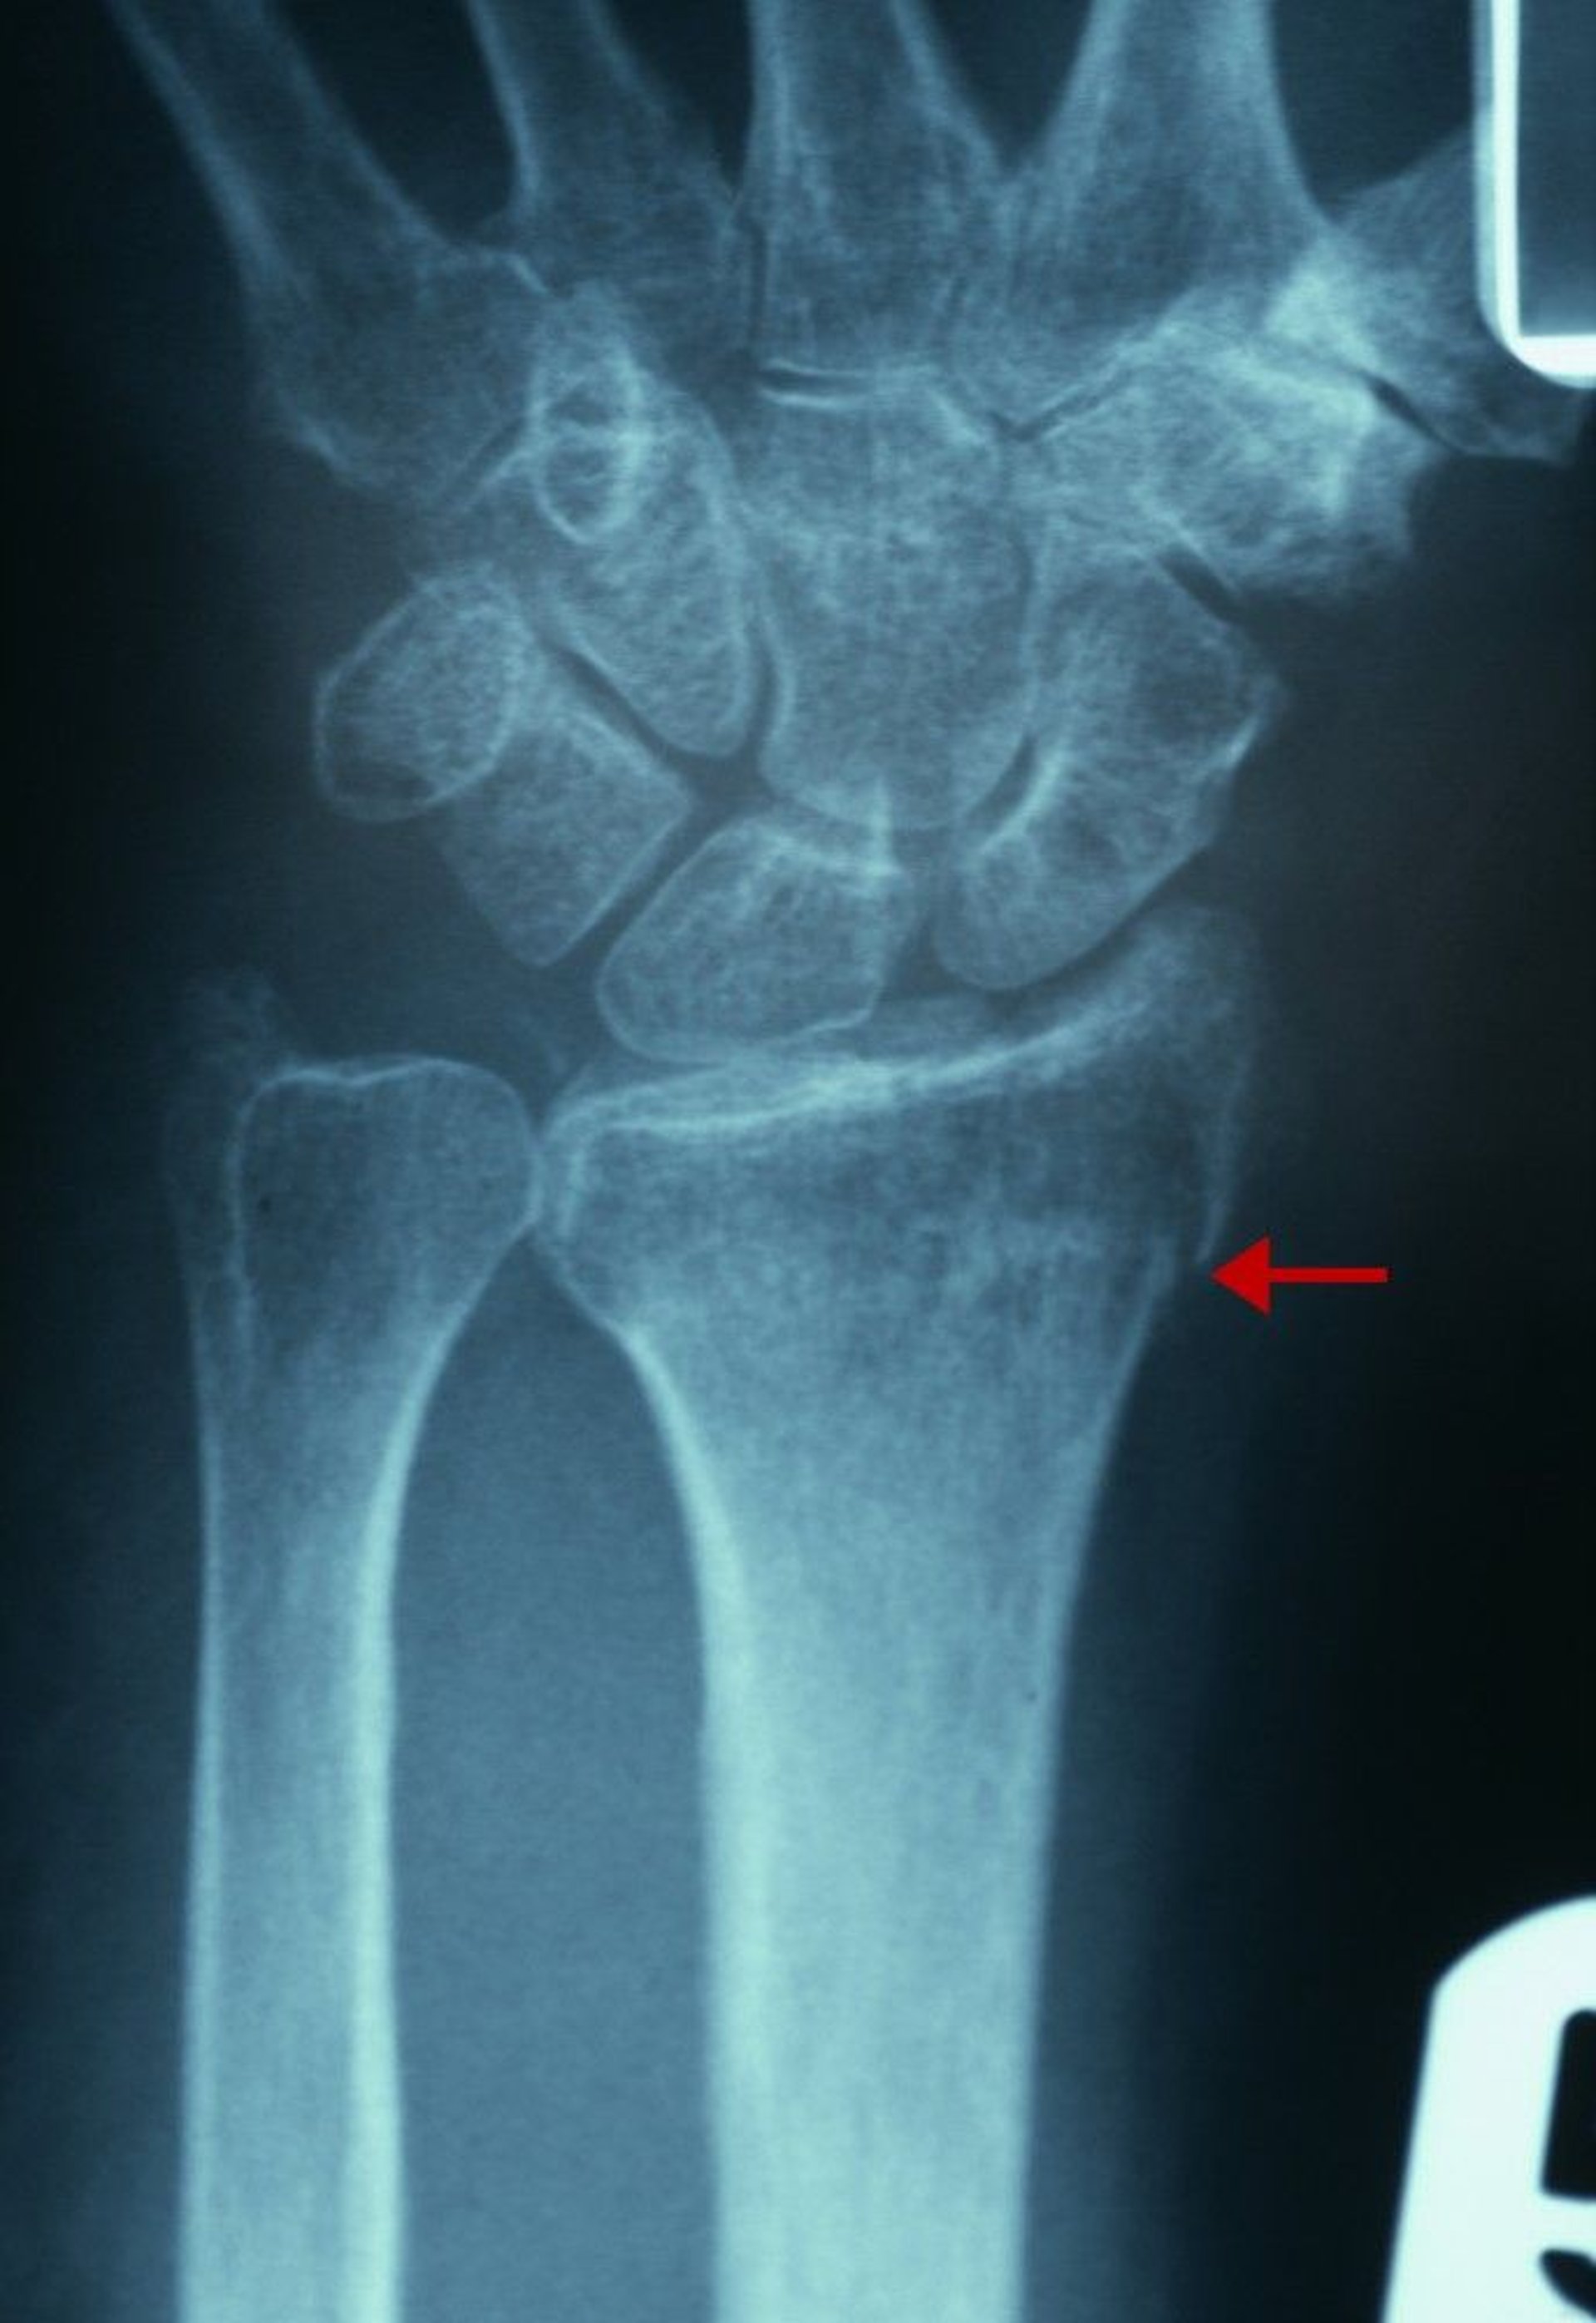

Subtle Distal Radius Fracture

Radiographic evidence of this fracture includes a break in the continuity of the cortex of the radial aspect of the distal radius (arrow) and an increase in trabecular density of the distal radius.